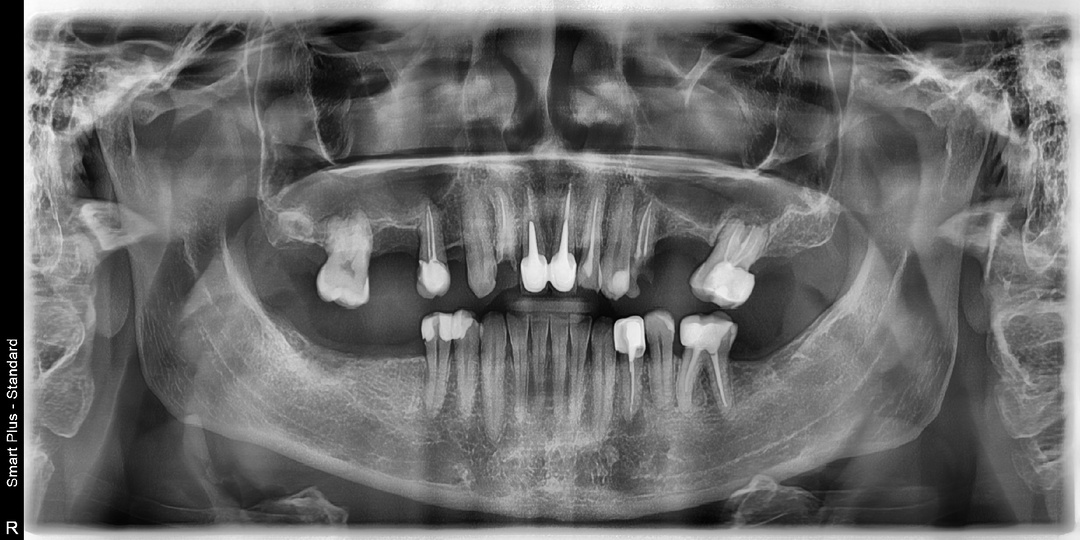

С каждым годом всё больше россиян едут восстанавливать зубы в Китай, особенно в город Хэйхэ, где работает государственная стоматологическая больница. Здесь действительно можно провести качественное протезирование за короткий срок и по разумной цене. Однако всё чаще появляются негативные отзывы от тех, кто возвращается из Китая с осложнениями, болями и разрушенными конструкциями. Причина почти всегда одна и та же — пациенты едут в Китай без предварительной диагностики, без панорамного рентгеновского снимка, без консультации врача-ортопеда. Панорамный рентгеновский снимок, или ОПТГ, позволяет врачу увидеть не только коронки зубов, но и внутренние процессы — воспаления у корней, кисты, гранулёмы, последствия неправильного лечения каналов, хронические очаги инфекции, скрытые переломы, патологические изменения костной ткани. Именно по этому снимку врач может точно сказать, какие зубы пригодны для протезирования, а какие требуют предварительного лечения или удаления. Без снимка любое протези